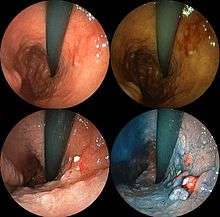

| A stomach ulcer that was diagnosed as cancer on biopsy and surgically removed. | |

Abnormal tissue seen in a gastroscope examination will be biopsied by the surgeon or gastroenterologist. This tissue is then sent to a pathologist for histological examination under a microscope to check for the presence of cancerous cells. A biopsy, with subsequent histological analysis, is the only sure way to confirm the presence of cancer cells.[27]

Various gastroscopic modalities have been developed to increase yield of detected mucosa with a dye that accentuates the cell structure and can identify areas of dysplasia. Endocytoscopy involves ultra-high magnification to visualise cellular structure to better determine areas of dysplasia. Other gastroscopic modalities such as optical coherence tomography are being tested investigationally for similar applications.[49]